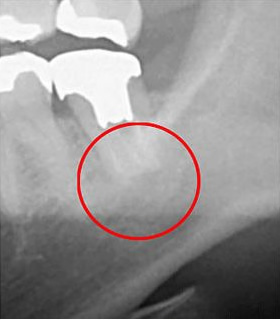

実際に「根管」の画像をご覧頂きましょう。歯の中にある黒い筋が根管です。